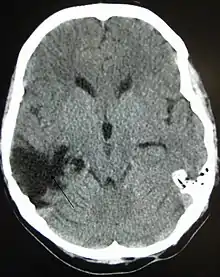

![]() TAC mostrando contusiones cerebrales, hemorragia intracraneal entre los hemisferios, hematoma subdural y fracturas craneales[1] | ||

En el TCE grave o severo (ECG 3-8) el paciente tiene un estado comatoso, no puede abrir sus ojos, seguir órdenes y sufre de lesiones neurológicas significativas. Por lo general tiene una neuroimagen anormal, es decir, a la tomografía computarizada (TAC/TC) se observa fractura del cráneo o hemorragia intracraneal. Estos pacientes requieren ingreso a la unidad de cuidados intensivos (UCI) y la toma de medidas urgentes para el control de la vía aérea, ventilación mecánica, evaluación o intervención neuroquirúrgica y monitorización de la presión intracraneal (PIC). La recuperación es prolongada y generalmente incompleta. Un porcentaje significativo de pacientes con TCE grave no sobrevive más de un año.[7][5]

Los hematomas epidurales son los que se localizan entre la lámina interna craneal y la duramadre. Como se ha mencionado están asociados con fracturas de cráneo y ruptura de la arteria meníngea media o sus ramas. Son más comunes en las regiones parietales y temporales y son raros en las regiones frontales y occipitales. Se encuentran entre el 8% y 10% en pacientes con TCE grave. En la TAC, se ven como lesiones hiperdensas y biconvexas y debido a que no existe un espacio entre la duramadre y el hueso no suelen propagarse a menos que superen la adherencia de la duramadre. Estos hematomas son raros en infantes debido a que el cráneo es deformable lo que les confiere una protección. Además son raros en adultos mayores de 60 años debido a la adherencia débil de la duramadre al cráneo.[15]

Los hematomas subdurales se encuentran entre la cara interna de la duramadre y la superficie cerebral. Se encuentra entre el 20% y el 25% en pacientes con TCE grave. Son el resultado de hemorragia en las venas anastomóticas de la corteza cerebral superficial o ruptura de los senos venosos o sus tributarios y se asocian con daño en el tejido cerebral subyacente. Más específicamente se ha demostrado que un buen número de estos hematomas se deben a la ruptura de venas puente parasagitales[31][32]. Normalmente se expanden en la mayor parte de la convexidad cerebral pero no pueden propagarse al hemisferio contrario debido a la existencia de la hoz del cerebro. Los hematomas subdurales se clasifican en agudos, subagudos o crónicos dependiendo de la aparición y duración de estos y su aspecto característico en la TAC:[15]

Las contusiones se encuentran en 20% al 25% de los pacientes con TCE grave. Son lesiones heterogéneas compuestas de zonas de hemorragia puntiforme, edema y necrosis que aparecen en las imágenes de TC como áreas de hiperdensidad puntiforme (hemorragias), con hipodensidad circundante (edema), suelen estar localizadas en la cara inferior del lóbulo frontal y la cara anterior del lóbulo temporal por su relación con el ala mayor del esfenoides. También se pueden encontrar en la superficie de impacto y en la superficie contraria a este, el llamado efecto golpe-contragolpe. Cuando estas evolucionan se parecen más a los hematomas intracerebrales y su ubicación depende el posible efecto de masa.